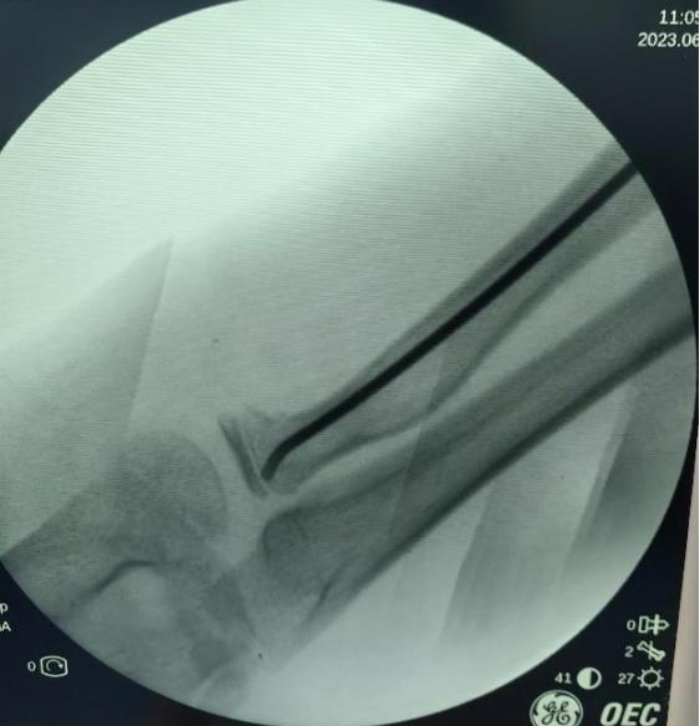

X線顯示:橈骨頸骨折端成角大于30°。骨科主任醫(yī)師錢鈞提醒,這種情況下后期發(fā)育畸形的可能性大,建議手術(shù)治療。

錢鈞組織骨科團(tuán)隊(duì)研討手術(shù)方案,決定為毅毅實(shí)施“橈骨頸骨折閉合復(fù)位彈性髓內(nèi)針內(nèi)固定術(shù)”。

采用該術(shù)不用切開(kāi)骨折端,創(chuàng)傷小,切口僅為1.5cm,術(shù)后疤痕小,不影響美觀,且手術(shù)時(shí)間短,固定穩(wěn)妥,利于肢體功能恢復(fù)。術(shù)后第2天毅毅即順利出院。